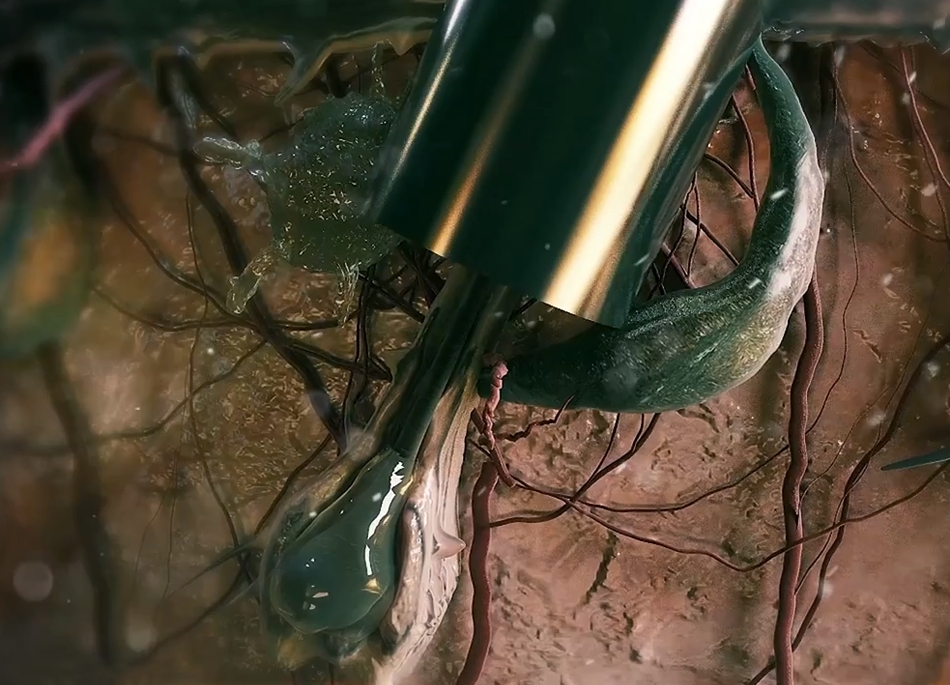

3d Medikal Tanıtım Filmleri - Medikal sektör için 3D ilaç tanıtım filmleri.